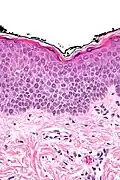

In der histologischen (lichtmikroskopischen) Untersuchung einer Gewebeprobe aus erkrankter Haut weist das Ekzem die Merkmale einer spongiotischen Dermatitis auf. Analog zum klinischen Bild zeigt sich ein charakteristischer Verlauf der Veränderungen:

Akute Phase: In der Oberhaut (Epidermis) zeigt sich eine Gefügelockerung durch ein interzelluläres Ödem (Spongiose), das bei starker Ausprägung zur Ausbildung von kleinen, aber auch größeren Blasen (Vesikel bzw. Bullae) führen kann.

Als Kratzeffekt besteht eine überschießende und eventuell auch gestörte Verhornung (Hyperkeratose bzw. Parakeratose) mit überliegender Schuppenkruste (parakeratotische Hornschicht mit eingeschlossenen Serumresten). Auch die oberen Anteile der Lederhaut (Dermis) sind durch ein Ödem gelockert, hier finden sich außerdem weitgestellte kleine Blutgefäße (Kapillaren). Um diese Gefäße bilden sich Ansammlungen aus Entzündungszellen, die sich hauptsächlich aus Lymphozyten und Histiozyten, nicht selten auch eosinophilen Granulozyten (Untergruppen der weißen Blutkörperchen) zusammensetzen. Lymphozyten wandern teilweise auch in die Epidermis ein (lymphozytäre Exozytose).

Als Reaktion auf den anhaltenden Entzündungsreiz und juckreizbedingtes Kratzen kommt es in der Folge zur Verbreiterung der Epidermis (Akanthose) mit Rückgang der Spongiose. Anfangs eventuell vorhandene größere Blasen gehen zurück, und es verbleiben nurmehr kleine Bläschen. Zumeist besteht jetzt eine ausgedehnte Parakeratose, und im Randbereich oberflächlicher epidermaler Defekte (Erosionen) können auch neutrophile Granulozyten (Untergruppe der weißen Blutkörperchen) in der Epidermis zu sehen sein. Dieses Zwischenstadium wird gelegentlich auch als subakute Phase bezeichnet.

Chronische Phase: es überwiegen die Zeichen der chronischen mechanischen Irritation mit Lichenifikation: epidermal zeigt sich eine deutliche Akanthose mit Verbreiterung der Granularzellschicht (Hypergranulose) und Hyperkeratose. Die Spongiose geht weiter zurück und kann in diesem Stadium nur noch sehr schwach ausgeprägt sein. Das der Epidermis unmittelbar unterliegende Bindegewebe der oberen Dermis (Stratum papillare) zeigt eine Vermehrung von Kollagenfasern (Fibrose), die senkrecht zur Epidermis ausgerichtet sind.[5]

-

Spongiose: Gefügelockerung der Epidermis mit sichtbaren Spalten zwischen den einzelnen Zellen durch interzelluläres Ödem -

Vesikelbildung: bei starker Spongiose lösen sich die Zellen voneinander und es bilden sich kleine Bläschen

Hyperkeratose: der Epidermis aufgelagert besteht eine verbreiterte Hornschicht. In der Dermis Kapillaren mit umliegenden Entzündungszellen

Parakeratose: die Hornschicht enthält Reste von Zellkernen als Zeichen der gestörten Verhornung